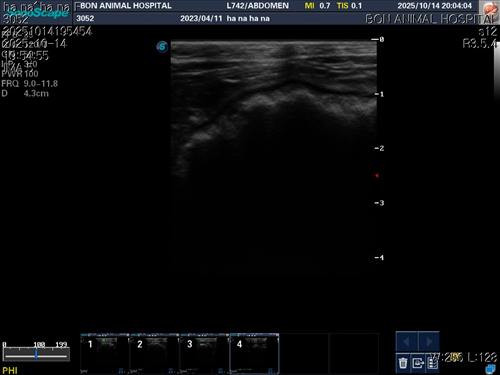

10월 10일 포도를 토해논후로 식욕저하 기력저하가 있어서 동물병원에 방문해서 엑스레이를 찍었는데 우선 지켜보자는 말과 소화제처방과 주사를 맞고 집왔습니다 그 후로도 안먹어서 12일에 동물병원에가서 혈액검사도 하고 수액도 맞았습니다 췌장쪽 수치가 좀 높아서 췌장쪽만 다시 검사했는데 수치는 괜찮았습니다 식욕촉진이랑 소화제처방 받아서 먹이는데 식욕저하도 여전하고 기력이 좀 없고 10일부터 14일까지 대변을 못보고있어서 14일에 병원에 가서 엑스레이랑 초음파를 했는데 장폐색일수도 있다는 말을 들었습니다 초음파상으로는 소장쪽 이물이 의심된다고 하셨어요ㅠ